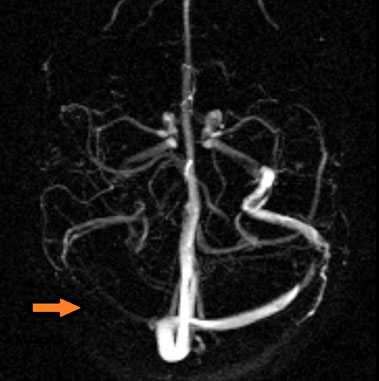

МР-венография - отсутствие визуализации кровотока в правом поперечном синусе и яремной вене.

МР-венография: тромбоз левого поперечного синуса. Отмечается потеря МР-сигнала от левого поперечного синуса.

МР-венография: тромбоз правого поперечного синуса. Отмечается потеря МР-сигнала от правого поперечного синуса.